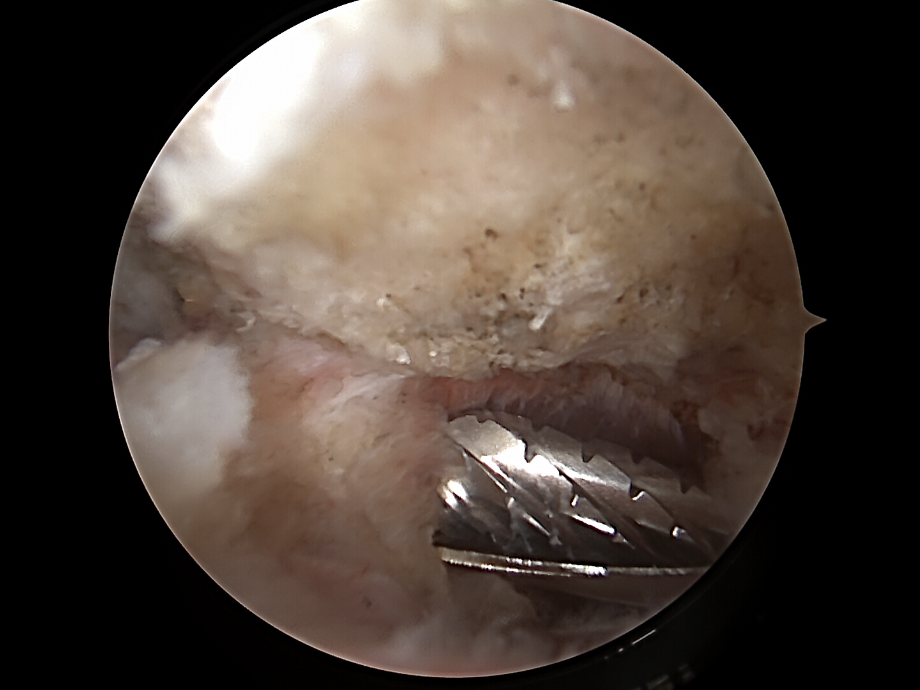

Dekompression

• Mit einer Fräse oder einem Shaver wird das  Akromion Schulterdach von innen geglättet (Akromioplastik).

• Gegebenenfalls wird auch das Coracoakromialband teilweise gespalten, um zusätzlichen Raum zu gewinnen.

Ziel: Erweiterung des subakromialen Gleitraums für die Sehnen.

ac gelenkresektion von dr. timmel von ortho-timmel.at